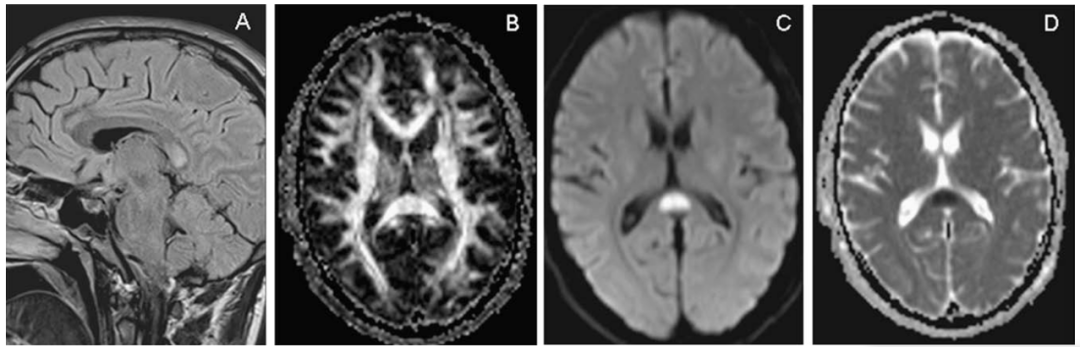

颅脑MRI矢状位FLAIR示胼胝体压部高信号(A)

DTI示同一部位胼胝体横向纤维受损(B)

DWI和ADC示胼胝体压部细胞毒性水肿(C、D)

颅脑MRI、DWI示:

双侧大脑半球皮层下白质、

胼胝体、双侧小脑中脚高信号